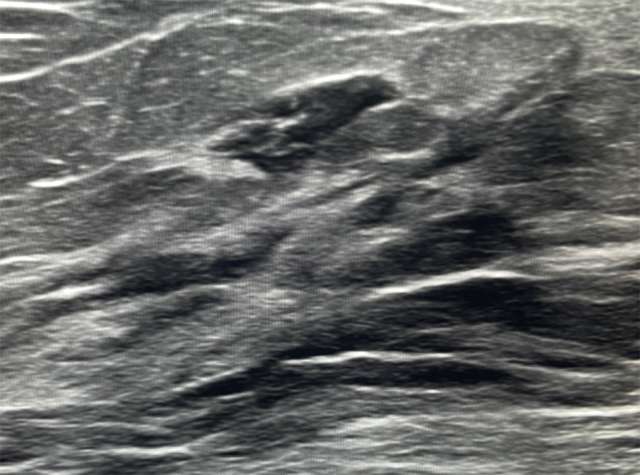

Ultrasound: Primary breast lymphoma have an unspecific appearance on ultrasound, ranging from a solitary, uncalcified, circumscribed, or indistinctly marginated mass. They are usually parallel in axis to the surrounding tissue, and are hypervascular. Posterior acoustic enhancement and echogenic rims may also be seen. SBL is usually hypoechoic or mixed echogenicity.